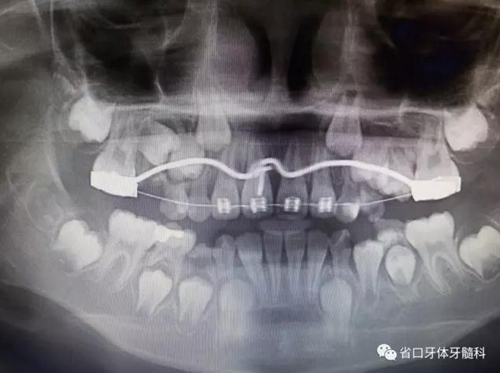

X線檢查:全景片

CBCT顯示右上中切牙埋伏阻生,牙軸呈水平位,冠向唇側(cè)、

根向腭側(cè),與鄰牙成90°夾角,牙根尚未發(fā)育完成,根端輕微彎曲。